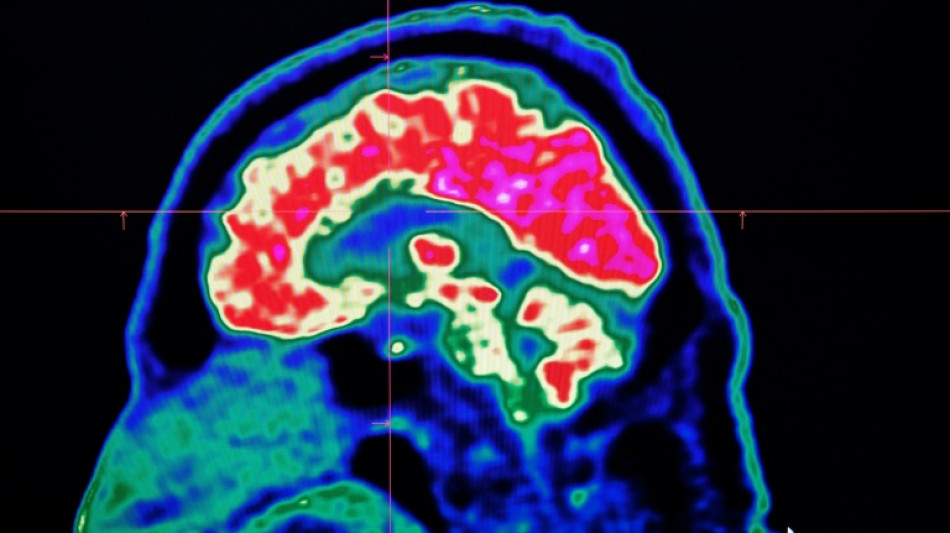

In 2021, health officials in New Brunswick launched an investigation involving 48 patients with a range of neurological symptoms but no apparent common illness. These included muscle spasms, memory loss, hallucinations and balance issues.

Some in the province of less than a million people began describing the condition as a mystery brain disease.